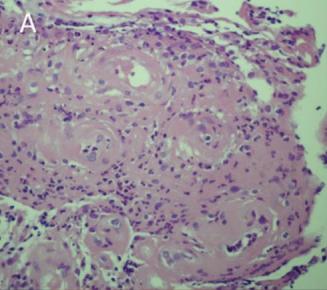

几天后,李先生的活检结果出来了,如下图所示:

图3. 活检结果活检检查出来了!

到底是不是癌?

据悉李医生三年前曾诊断ANCA相关性血管炎

难道肿块与血管炎有关系?